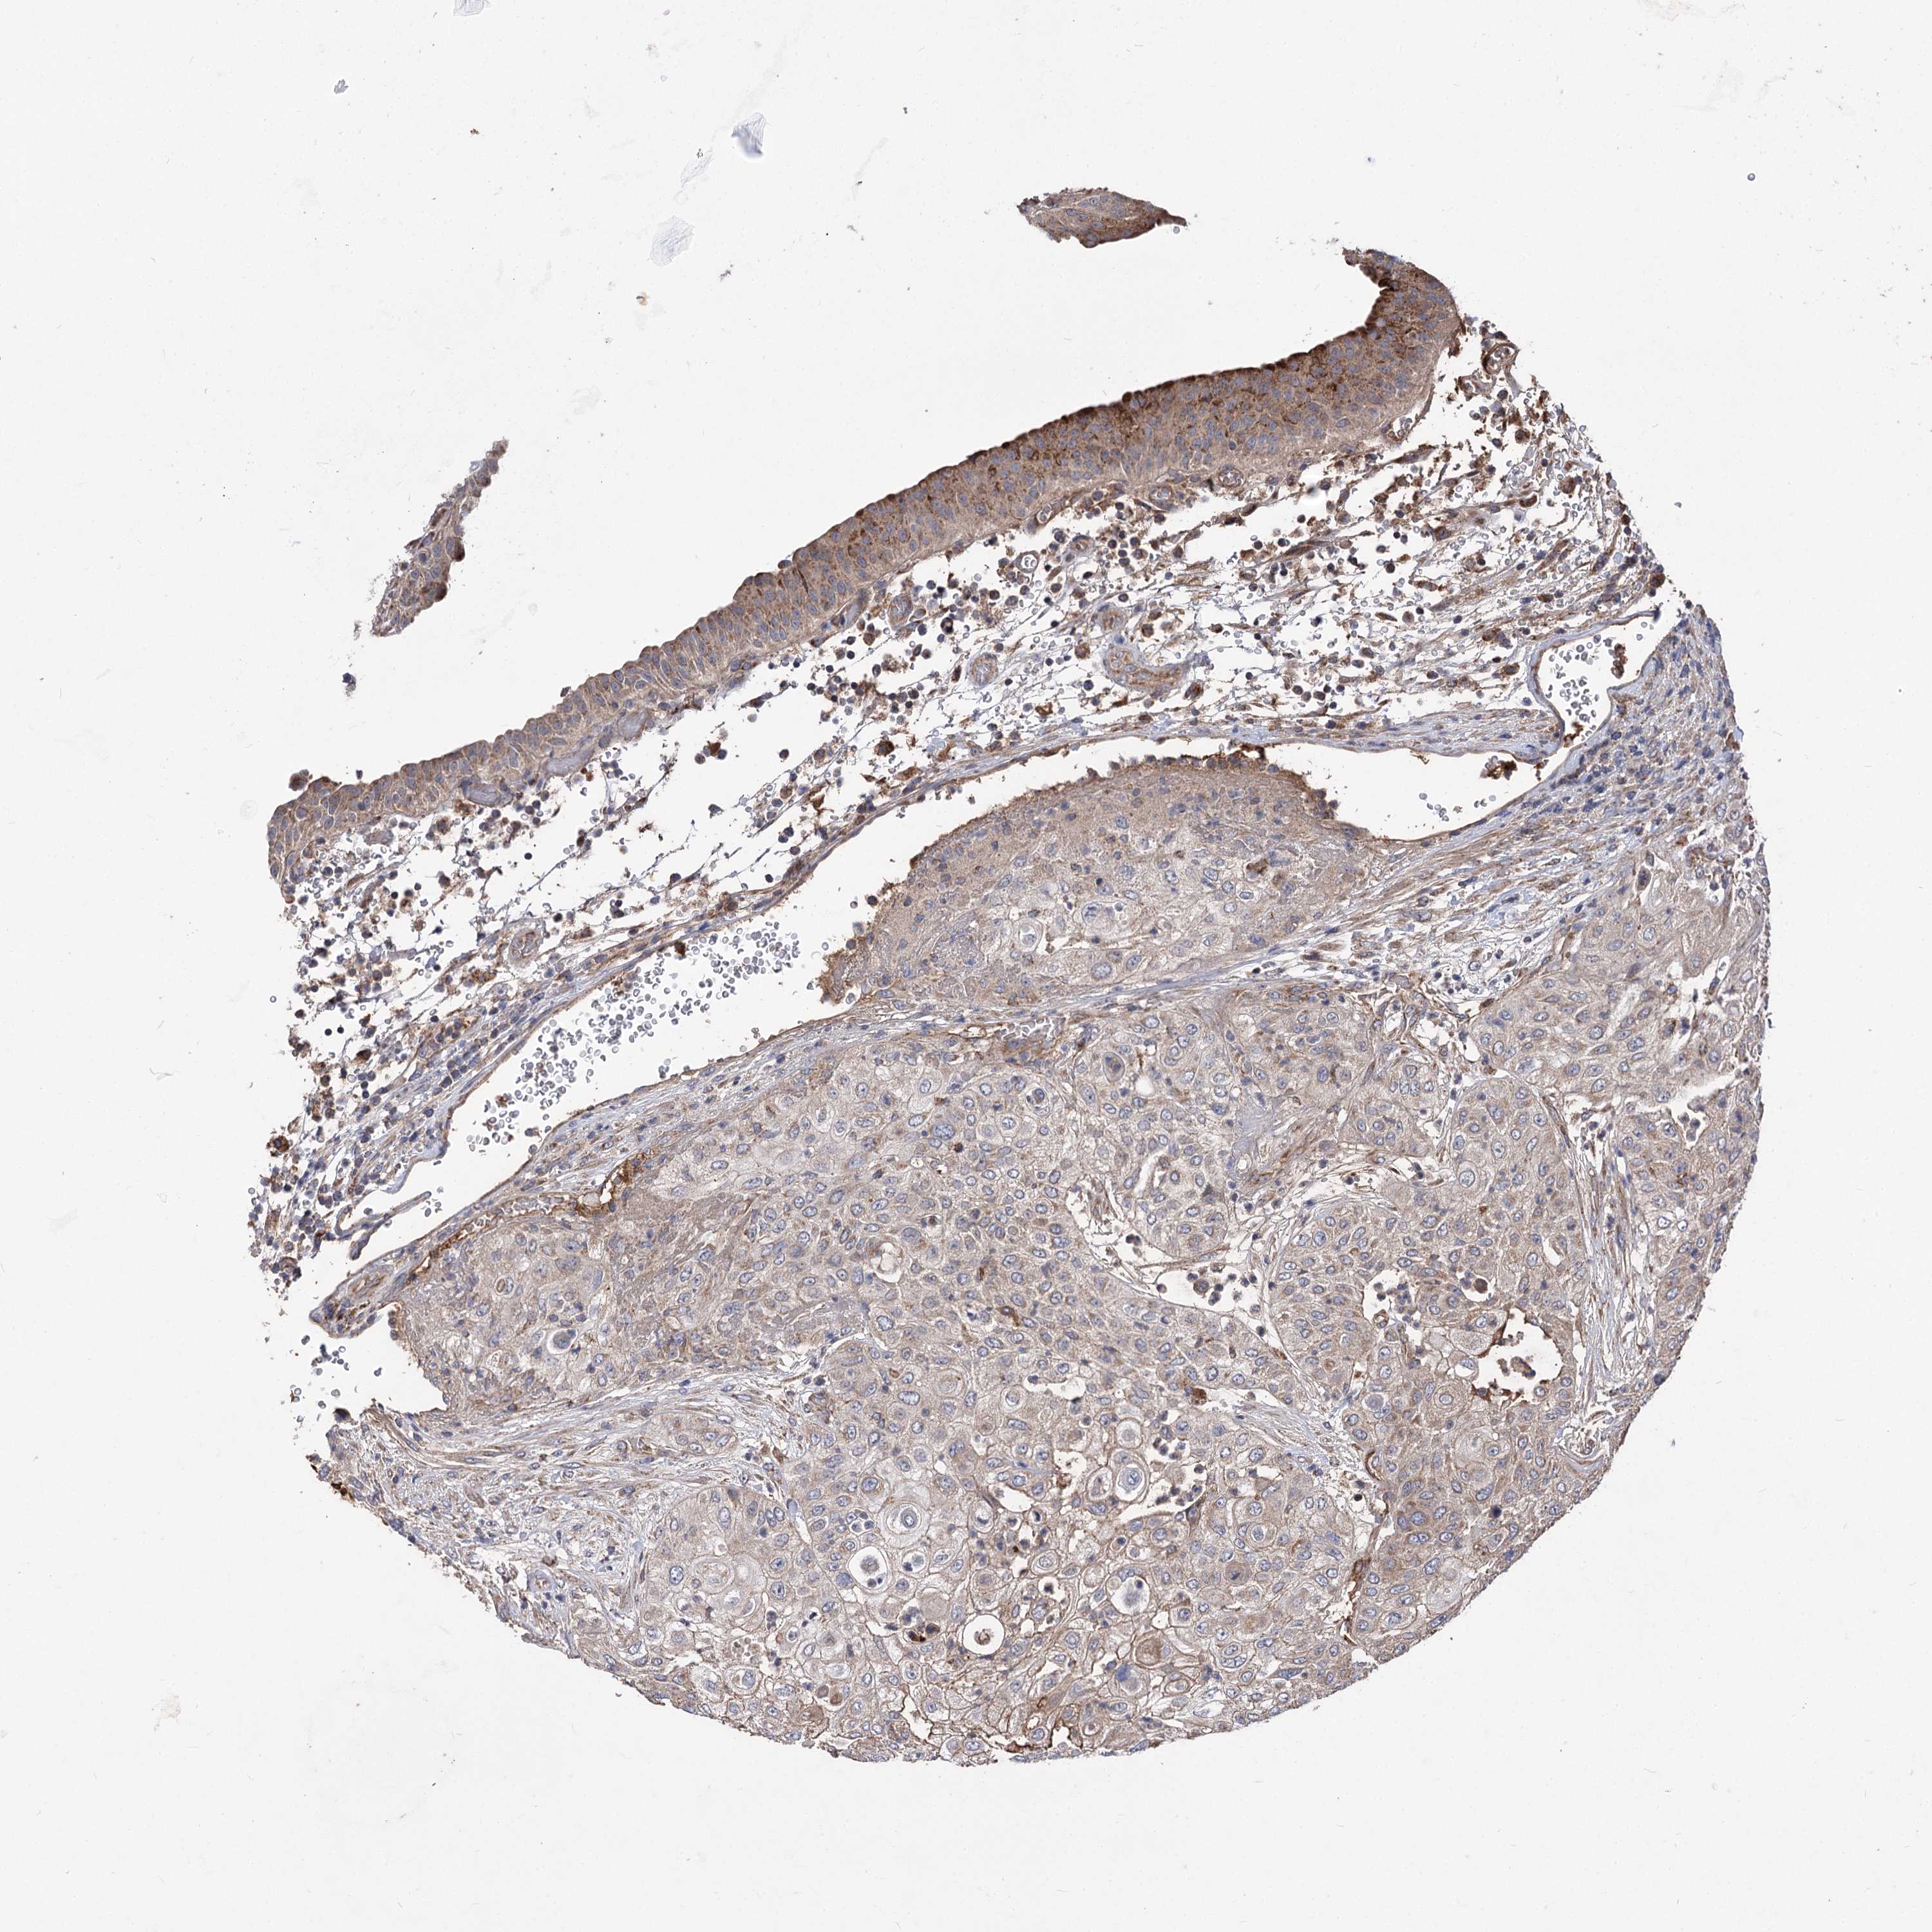

UROTHELIAL CANCER - Protein expressioni

A mouse-over function shows sample information and annotation data. Click on an image to view it in a full screen mode. Samples can be filtered based on level of antibody staining by selecting one or several of the following categories: high, medium, low and not detected. The assay and annotation is described here.

Note that samples used for immunohistochemistry by the Human Protein Atlas do not correspond to samples in the TCGA dataset.

Antibody stainingi

Antibody staining in the annotated cell types in the current human tissue is reported as not detected, low, medium, or high, based on conventional immunohistochemistry profiling in selected tissues. This score is based on the combination of the staining intensity and fraction of stained cells.

Each image is clickable and will lead to virtual microscopy that enables deeper exploration of all samples and also displays staining intensity scores, fraction scores and subcellular localization as well as patient and tissue information for each sample.

Antibody HPA038469

Antibody CAB022664

Antibody CAB034035

Staining

High

Medium

Low

Not detected

Intensity

Strong

Moderate

Weak

Negative

Quantity

>75%

75%-25%

<25%

None

Location

Nuclear

Cytoplasmic/membranous

Cytoplasmic/membranous,nuclear

Urothelial carcinoma, High grade

Urothelial carcinoma, Low grade